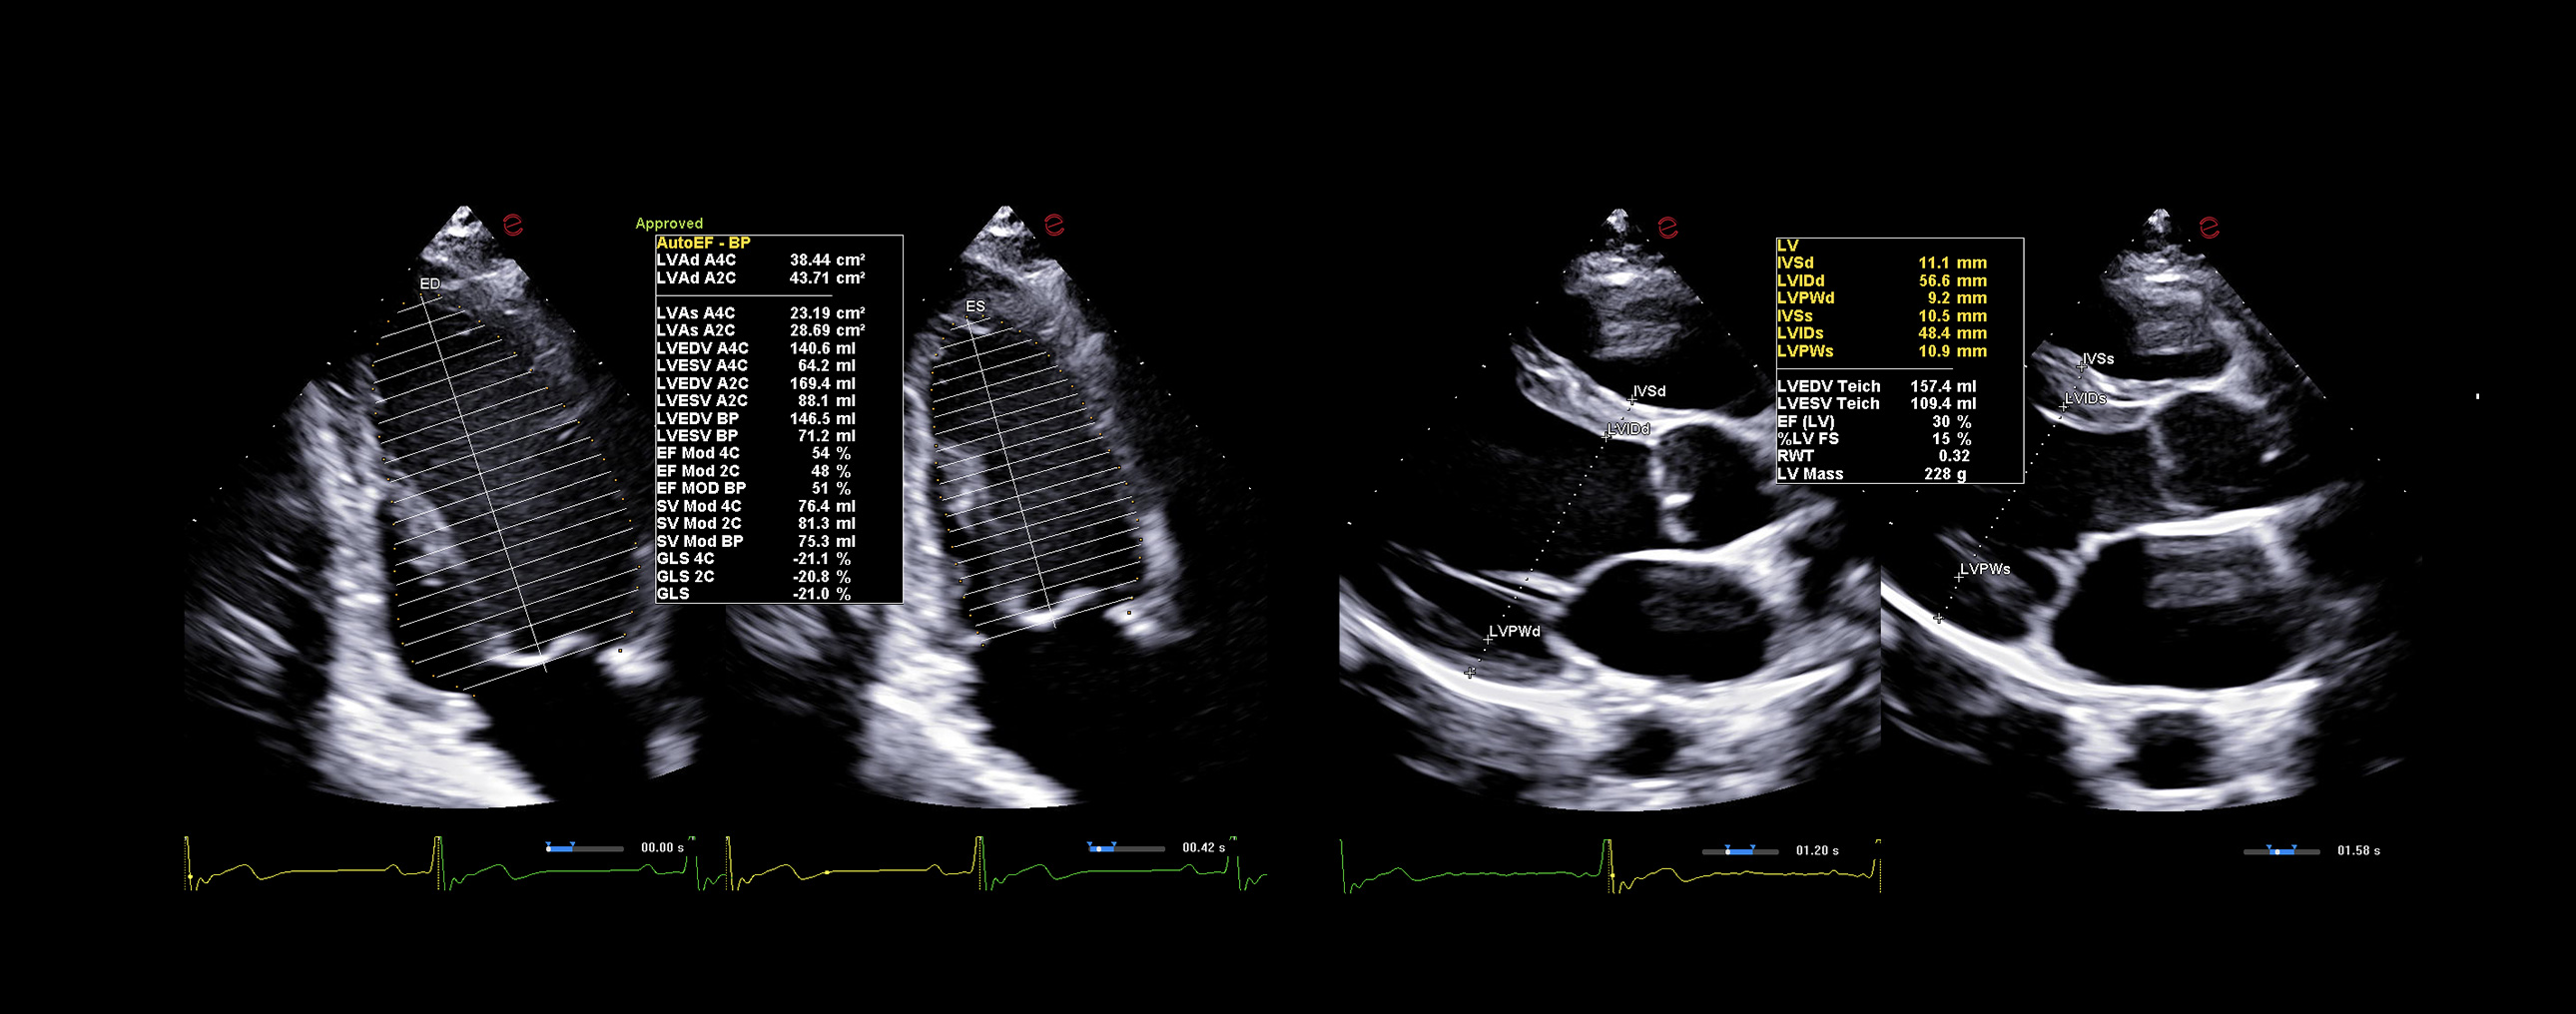

AI-based cardiac measurements for speed and consistency

Esaote’s AutoEF and AutoCM tools are designed to bring a step ahead in the device use experience. With advanced AI algorithms, AutoEF automatically recognizes apical views and traces endocardial borders offering a proposal of left ventricular volumes and ejection fraction in just seconds. AutoCM complements this by automatically suggesting ventricular wall thickness, internal diameters, and derived values such as LV mass and fractional shortening directly from parasternal views. Moreover, AutoCM assists cardiologists by automatically recommending a calculation of the E/A wave ratio of the mitral valve, providing crucial information on diastolic function.

Together, these tools help clinicians to obtain accurate, guideline-aligned measurements in a fast way, maintaining diagnostic evidence at the top. AutoEF and AutoCM automate key functional and structural measurements—such as ejection fraction, LV volumes, wall thickness, and LV mass— making a smooth workflow, especially in high-throughput clinics.